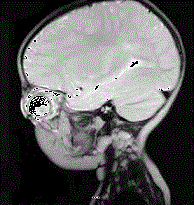

男,3岁,家长发现右眼瞳孔发白3个月(如图),眼眶CT如图,对该病描述错误的是 ( ) A、90%发生于3岁以前B、男性多于女性C...

问题 男,3岁,家长发现右眼瞳孔发白3个月(如图),眼眶CT如图,对该病描述错误的是 ( )

选项 A、90%发生于3岁以前 B、男性多于女性 C、可出现钙化灶 D、是儿童最常见的原发性眼内恶性肿瘤 E、双眼发病约占30%~35%

答案 B